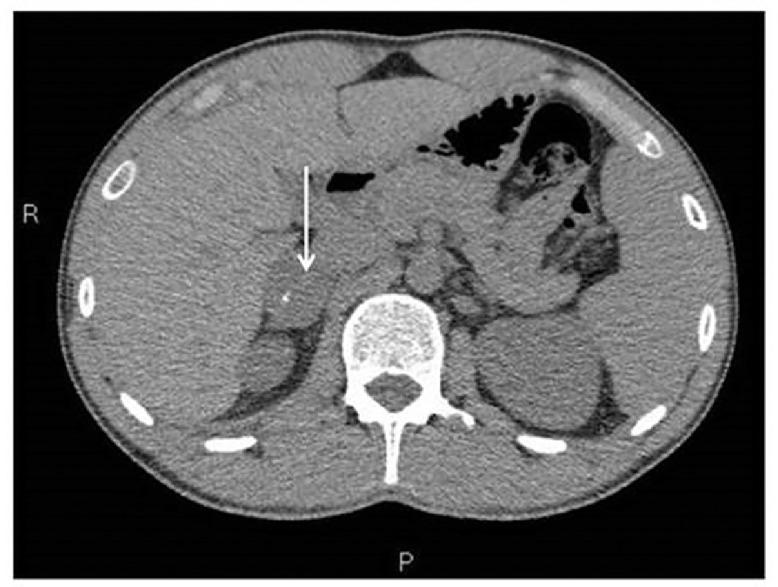

Peripheral neuroblastic tumors are extremely rare in the adult with less just over 20 cases involving adrenal gland described in the literature. We reported herewith the case of a 22-year-old young male who presented with epigastric pain and diarrhea. Imaging studies documented a 3.5cm x 3cm x 4cm solid well-circumscribed right adrenal mass, of heterogeneous structure and with fine calcifications. The lesion turned negative at MIBG scintigraphy. A right robotic-assisted adrenalectomy was performed leading to complete excision of the lesion without complications. Histology was consistent with intermixed stroma-rich ganglioneuroblastoma. A wait-and-see strategy was considered adequate. Two years after diagnosis patient is alive disease-free. Although the definitive diagnosis of a peripheral neuroblastic tumor is obtained after histopathological analysis, CT, and MRI are helpful to further characterize masses and useful in pretreatment risk stratification. Clinicians should be aware of the possibility of GNB development in adult population and its malignant potential.

外周神经母细胞瘤在成人中极为罕见,文献中报道的累及肾上腺的病例仅有20多例。我们在此报告一例22岁年轻男性,表现为上腹部疼痛和腹泻。影像学检查发现右肾上腺有一个3.5厘米×3厘米×4厘米的实性、边界清晰的肿块,结构不均质,有细小钙化。该病变在间碘苄胍(MIBG)闪烁扫描中呈阴性。实施了机器人辅助右肾上腺切除术,病变被完整切除,无并发症。组织学检查结果符合富含间质的混合型神经节神经母细胞瘤。采取观察等待策略被认为是合适的。诊断两年后,患者存活且无疾病。虽然外周神经母细胞瘤的明确诊断需经组织病理学分析得出,但CT和MRI有助于进一步明确肿块特征,且对治疗前风险分层有用。临床医生应意识到成人发生神经节神经母细胞瘤的可能性及其恶性潜能。